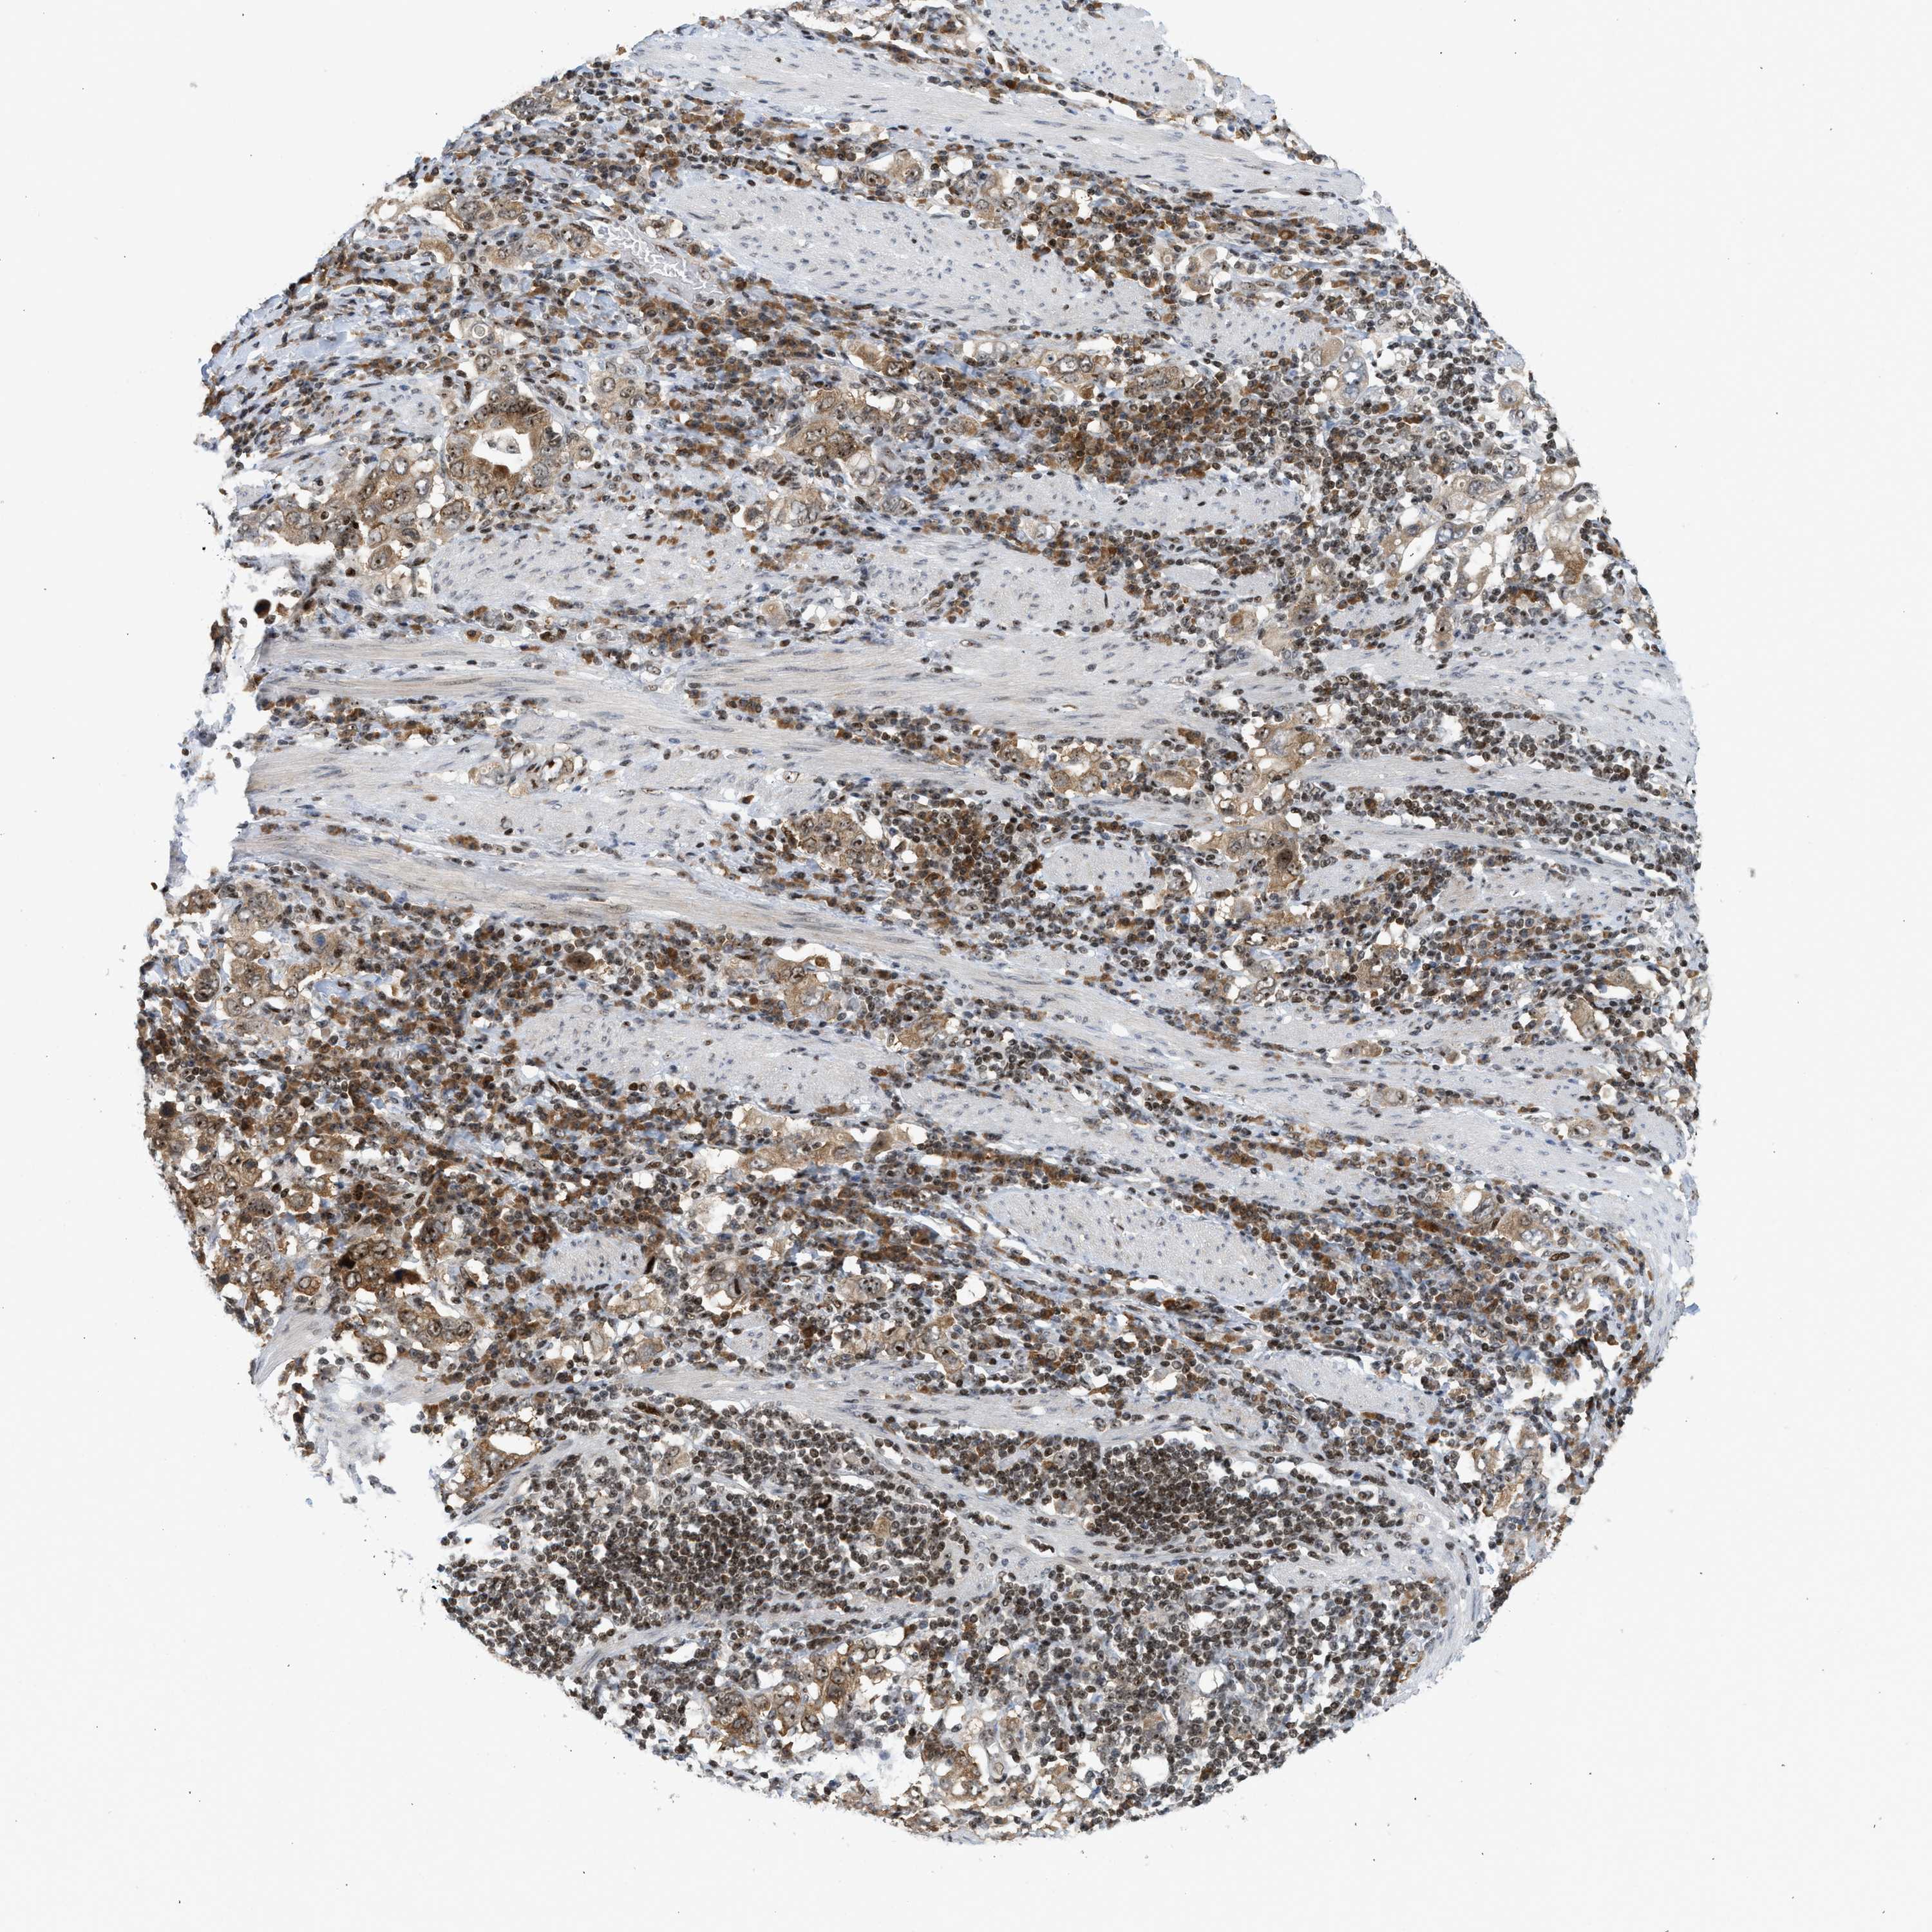

STOMACH CANCER - Protein expressioni

A mouse-over function shows sample information and annotation data. Click on an image to view it in a full screen mode. Samples can be filtered based on level of antibody staining by selecting one or several of the following categories: high, medium, low and not detected. The assay and annotation is described here.

Note that samples used for immunohistochemistry by the Human Protein Atlas do not correspond to samples in the TCGA dataset.

Antibody stainingi

Antibody staining in the annotated cell types in the current human tissue is reported as not detected, low, medium, or high, based on conventional immunohistochemistry profiling in selected tissues. This score is based on the combination of the staining intensity and fraction of stained cells.

Each image is clickable and will lead to virtual microscopy that enables deeper exploration of all samples and also displays staining intensity scores, fraction scores and subcellular localization as well as patient and tissue information for each sample.

Antibody HPA016736

Staining

High

Medium

Low

Not detected

Intensity

Strong

Moderate

Weak

Negative

Quantity

>75%

75%-25%

<25%

None

Location

Nuclear

Cytoplasmic/membranous

Cytoplasmic/membranous,nuclear

Adenocarcinoma, NOS